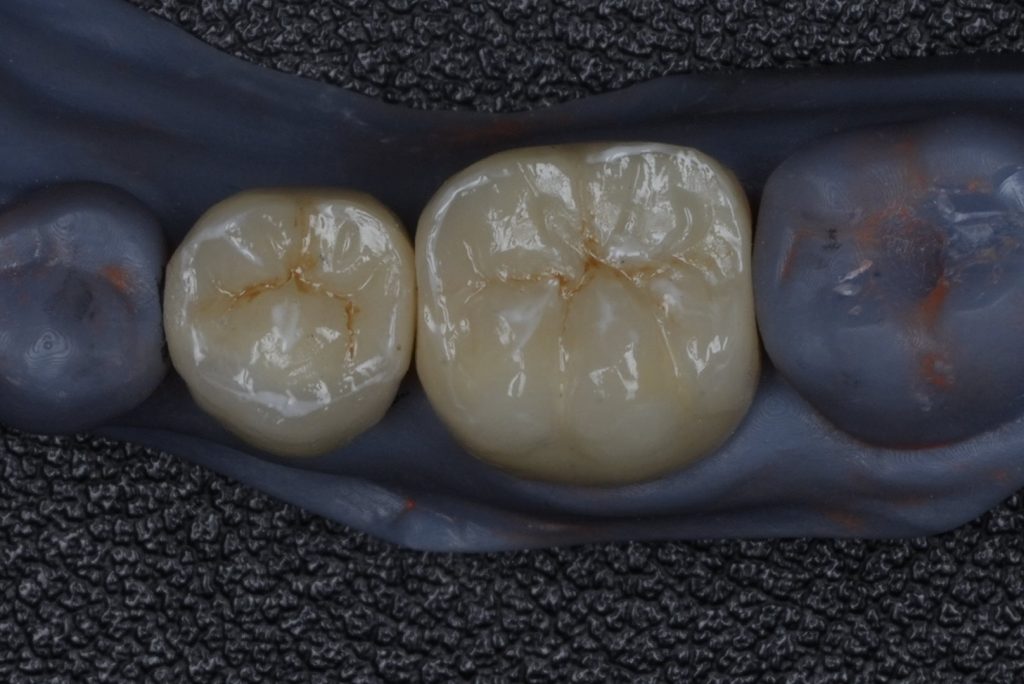

A full-coverage zirconia crown was fabricated to mimic occlusal morphology (Fig 4). Try-in confirmed marginal adaptation and occlusal contacts. Final bonding performed with Panavia V5 resin cement under isolation.

- Fig 4: Monolithic zirconia crowns ready for cementation.